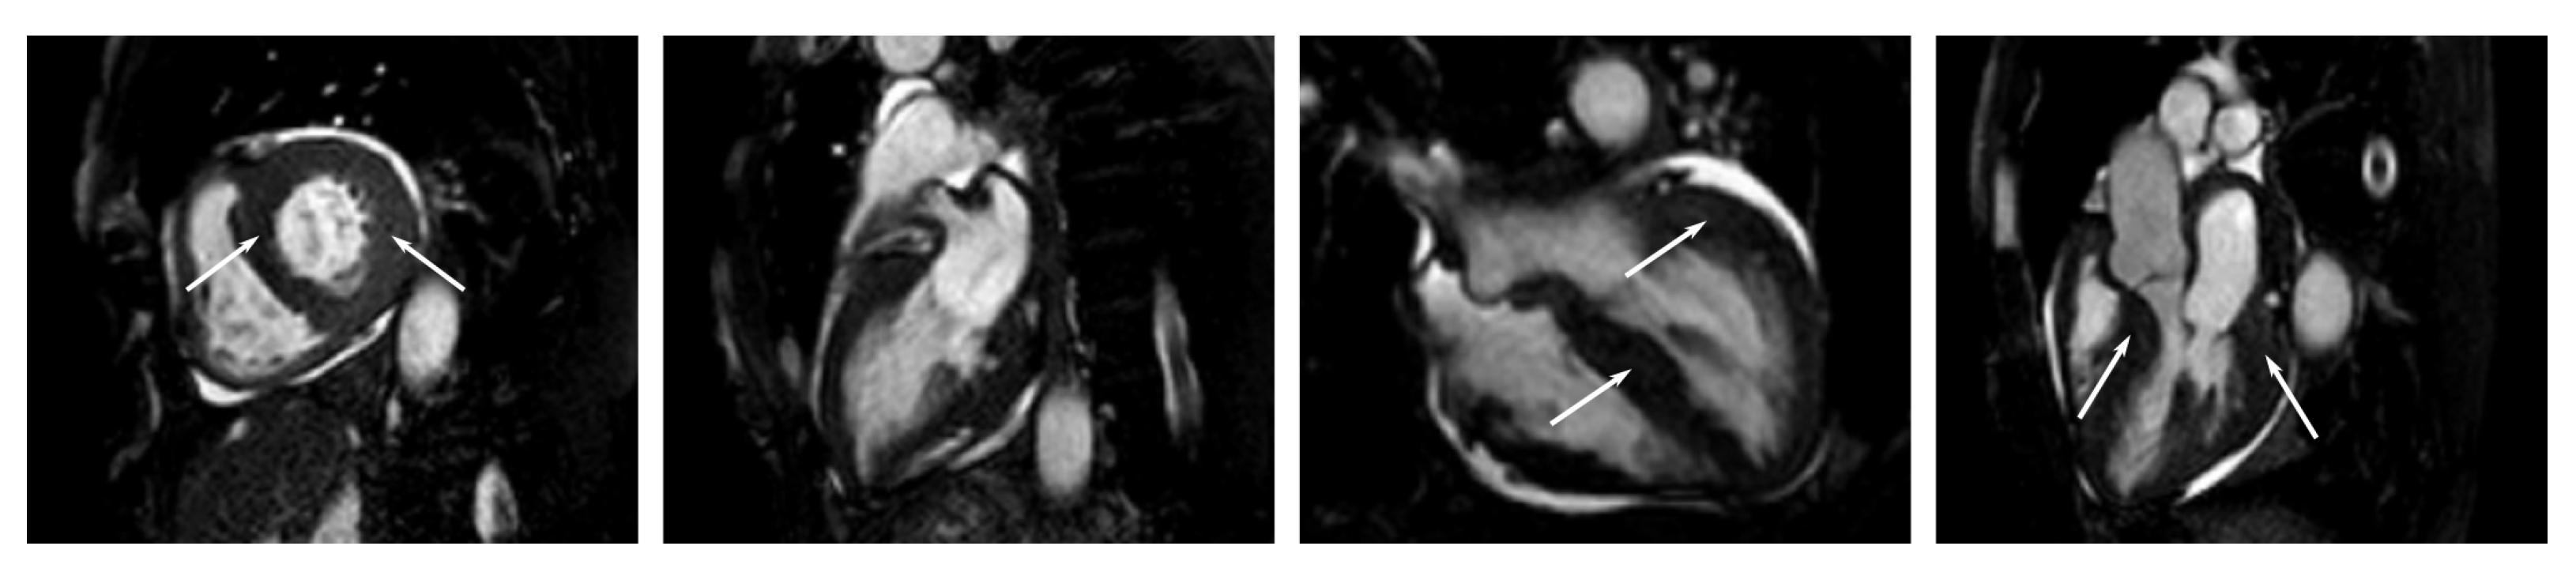

Appendix C. Example Images

- Short-axis images from the apex to the base at different stages of the cardiac cycle;

- Long-axis, two-chamber images at different stages of the cardiac cycle (heart beat);

- Long-axis, three-chamber images at different stages of the cardiac cycle;

- Long-axis, four-chamber images at different stages of the cardiac cycle.